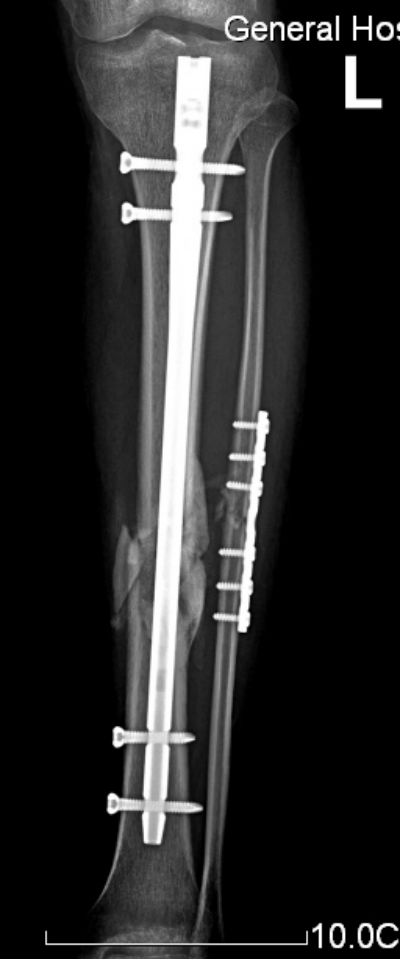

交锁髓内钉有较好的抗旋转、抗压缩作用,固定稳定性好,符合生物学固定原则(BO),在四肢长骨中应用广泛。

固定骨折的力臂比钢板长,作用力均匀分散在整个骨干的中轴上,不易发生折弯变形。

锁钉使骨干从上到下形成一体,防止缩短和旋转,对骨折的固定达到最大的稳定性。

胫骨中1/3稳定型骨折:横形骨折、短斜形骨折、假关节。

胫骨中部60%长度内的不稳定性骨折:干骺端附近的骨折、长螺旋形骨折、节段性骨折、粉碎性骨折、骨折伴骨缺损。

多用于胫骨中段骨折。尽管也可用于胫骨近端和远端骨折,但并发症发生率较高,易发生畸形愈合。